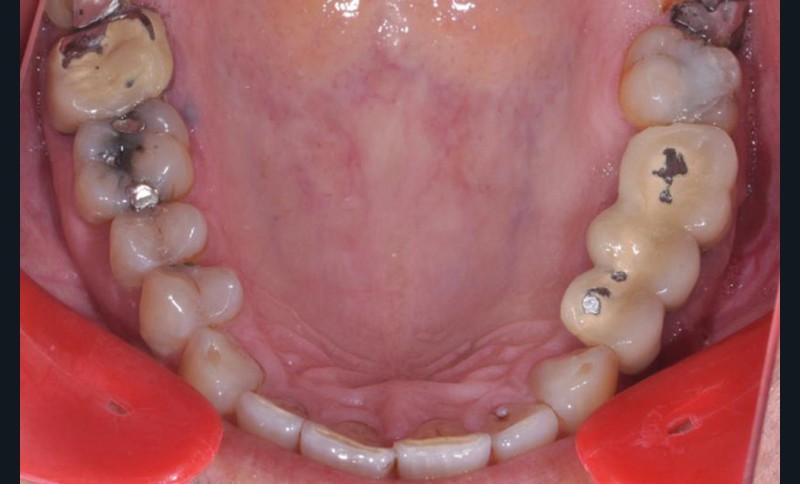

Présentation du cas clinique (fig. 1 à 3)

Le patient, âgé de 58 ans, présente un encombrement dentaire mandibulaire de 5 mm dans un contexte squelettique hypodivergent.

À la radiographie panoramique, on constate une lésion apicale sur 15 et une atteinte inter radiculaire sur 16 ainsi qu’une légère rotation de 21 sans gêne pour le patient.